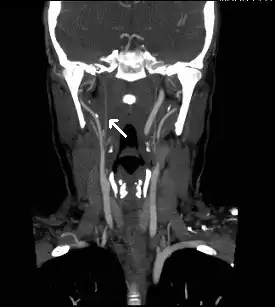

Carotid vessels with complete occlusion arrow